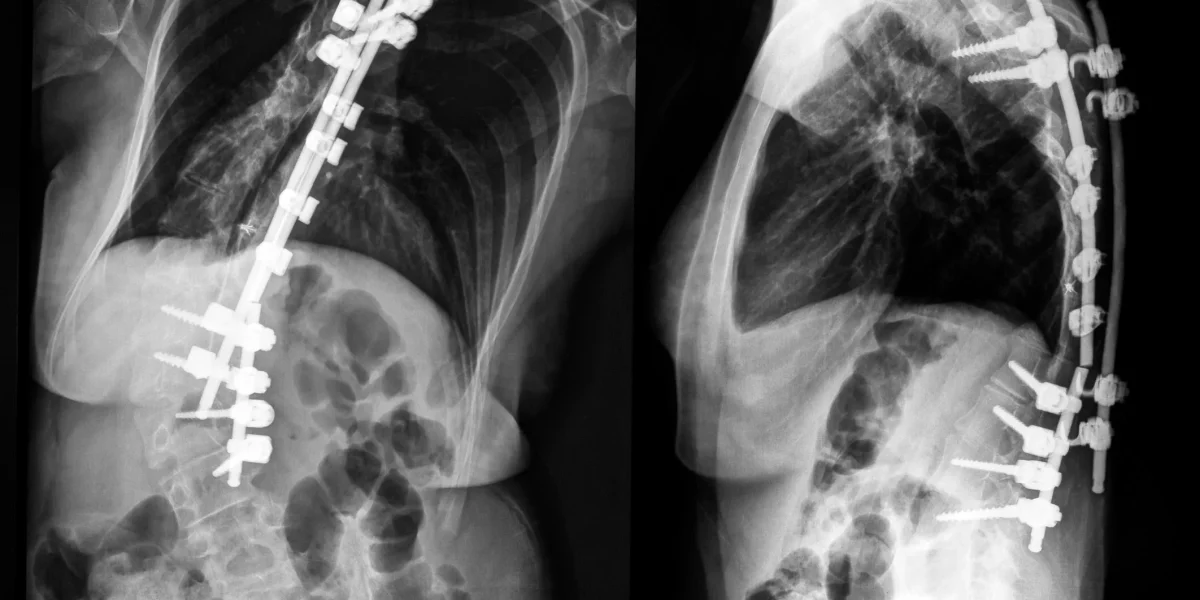

X-ray images showing spinal fusion with metal rods and screws in the spine.

Procedures like open spine surgery or spinal fusion often create more trauma than they solve.

Fusions, in particular, restrict natural motion, accelerate adjacent disc degeneration, and have a

high failure rate over time.

By contrast, Deuk Laser Disc Repair is a motion-preserving, minimally invasive procedure that

removes damaged disc tissue and leaves healthy structures intact. No hardware. No fusion.